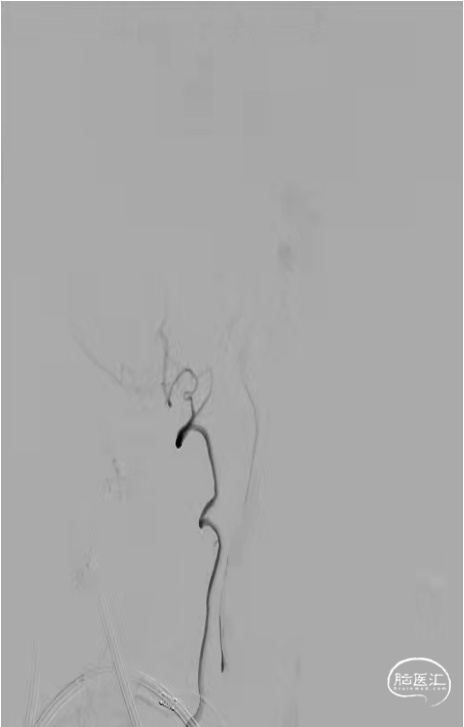

术前DSA(2021-10-12我院):左侧椎动脉标准正侧位造影及三维重建示:基底动脉尖部动脉瘤,血管直径2.2mm,动脉瘤2.8mm*2.5mm。

DSA(2021-10-12我院):右侧椎动脉造影:右侧椎动脉纤细,V4段以远显影欠佳。

R-Pcom通路建立:在路图下,Synchro-14(0.014in×200cm)微导丝携带支架微导管Excelsior SL-10经左侧股动脉建立好的入路超选入右侧后交通动脉内并至左侧大脑后P1段以远,用于横行放置支架。

LVA通路建立:Synchro-14(0.014in×200cm)微导丝携带另一根弹簧圈微导管Excelsior SL-10经右侧股动脉建立好的入路经左侧椎动脉超选入基底动脉尖动脉瘤瘤体内,用于弹簧圈填塞。

双微导管到位,调整为最佳工作位后,于路径图下,经弹簧圈微导管Excelsior SL-10送入第一枚Target 360 SOFT弹簧圈。同时经支架微导管Excelsior SL-10送入1枚Neuroform Atlas 无头(3mm×21mm)支架 。

准确定位并完全覆盖瘤颈口后释放支架。